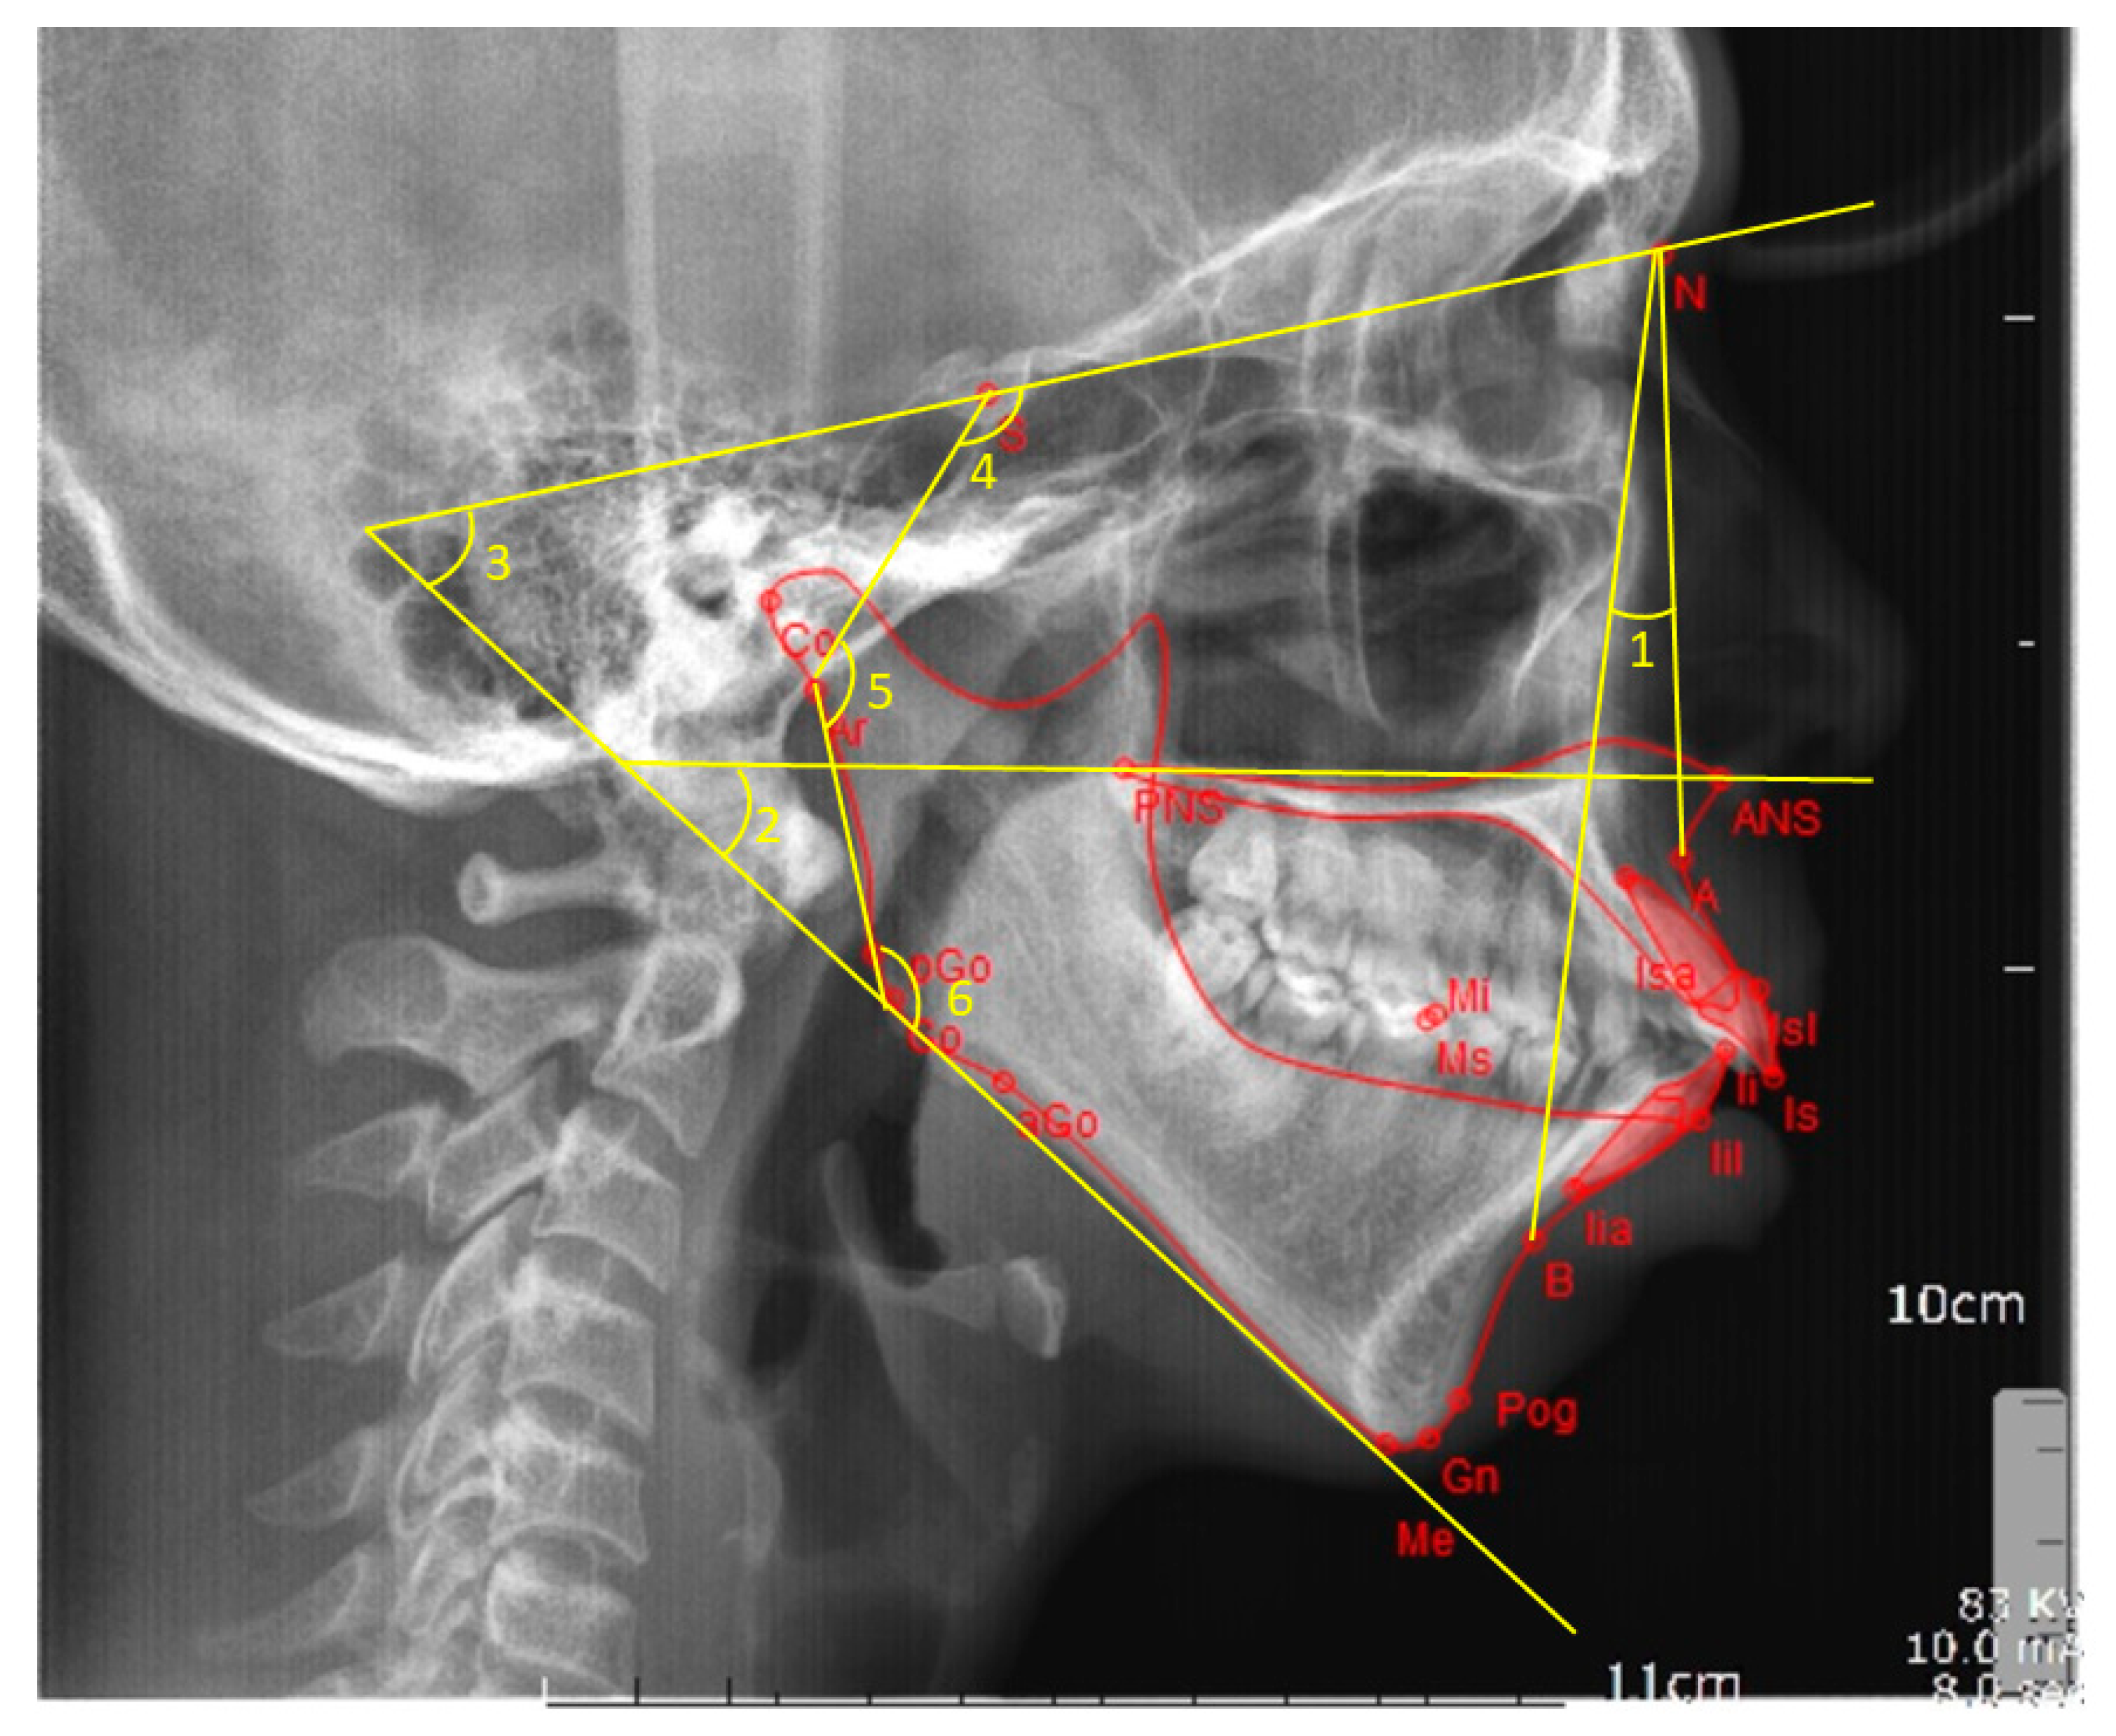

Figure 1.

Angular cephalometric measurements. 1 = ANB angle, 2 = intermaxillary angle, 3 = mandibular plane angle, 4 = saddle angle, 5 = articular angle, and 6 = gonial angle.